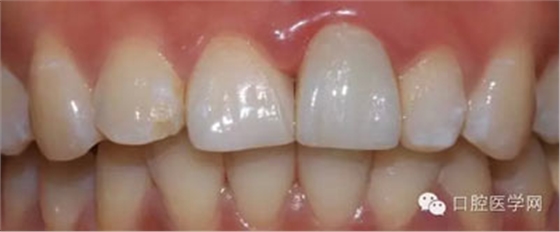

檢查:21金屬烤瓷冠修復(fù),顏色及形態(tài)與鄰牙不協(xié)調(diào),牙齦有輕微發(fā)黑,扣痛(-)、松動(dòng)度(-);11近中鄰面齲壞

術(shù)前照